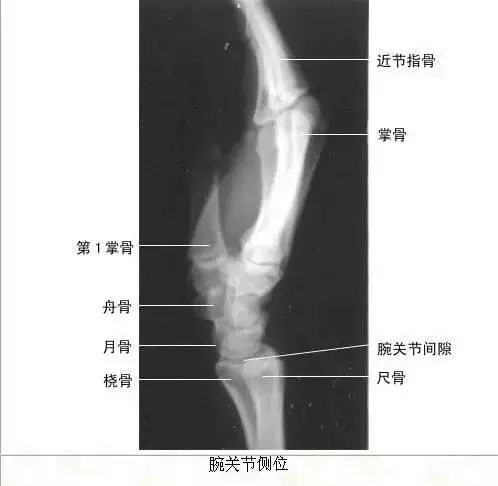

【实用干货】人体体表标志定位与解剖(含人体解剖图)